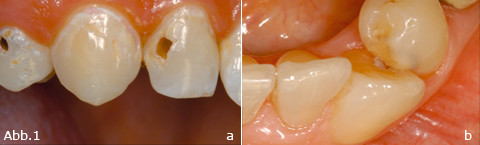

Die Diagnose der Zahnkaries zählt zu den primären Aufgaben des Zahnarztes und stellt eine Herausforderung im zahnärztlichen Alltag dar. Neben...

Die Diagnose der Zahnkaries zählt zu den primären Aufgaben des Zahnarztes und stellt eine...